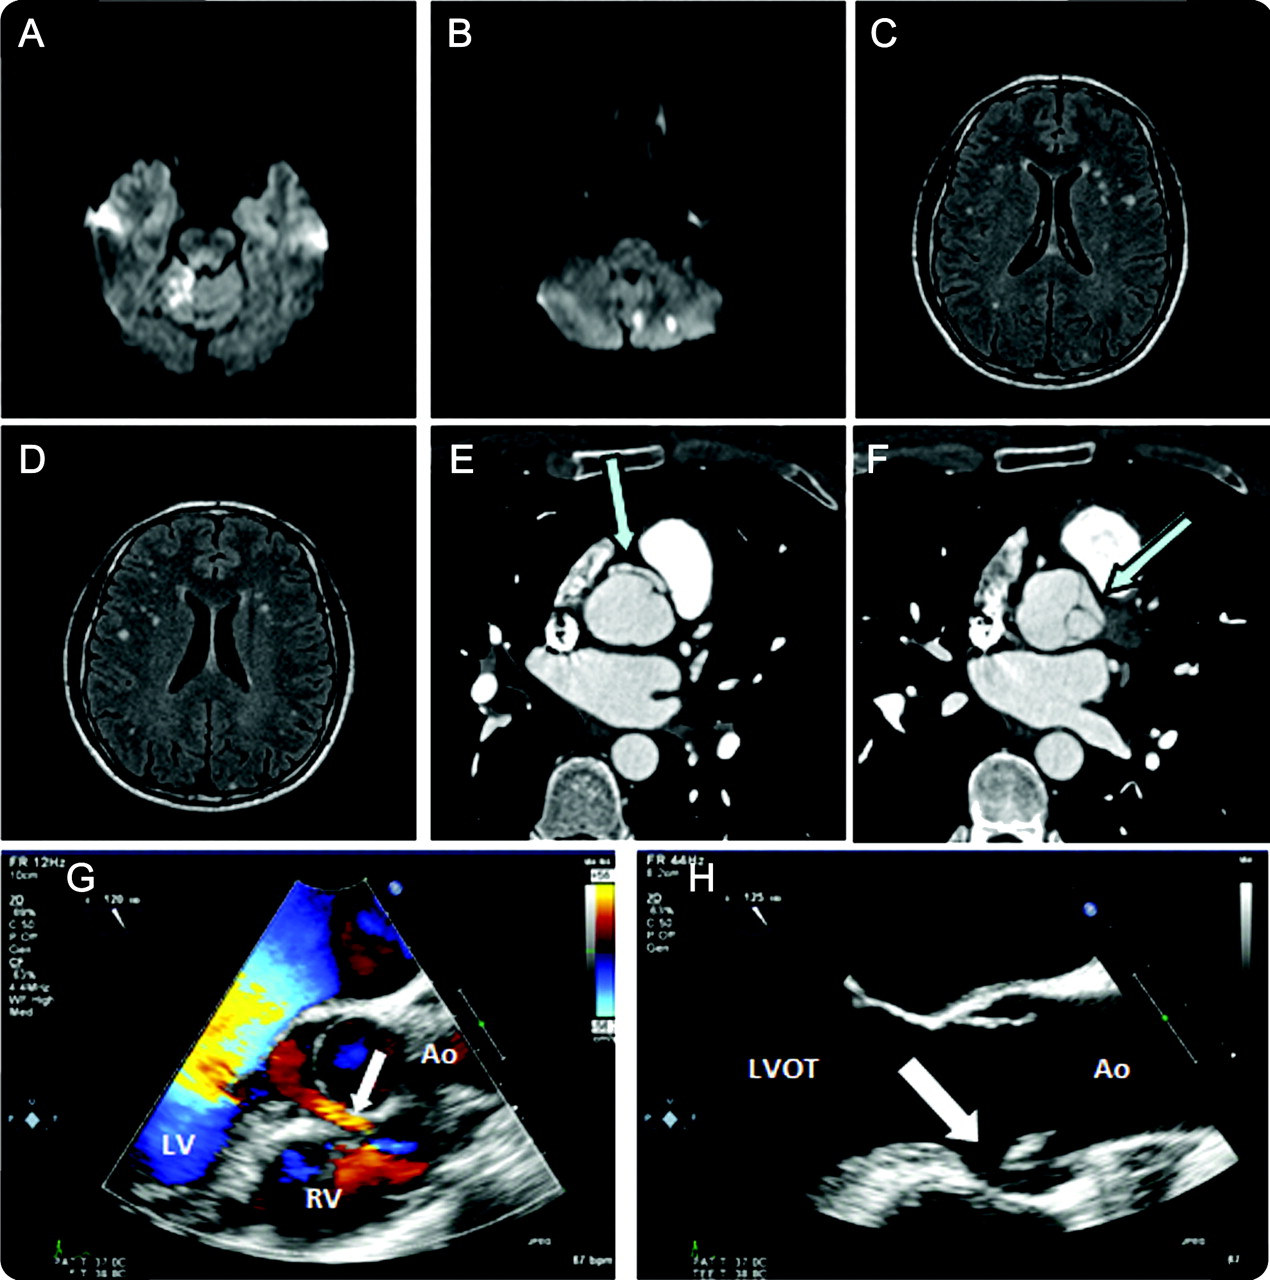

一个42岁的男人出现急性共济失调造成栓塞中风没有经典的血管危险因素但揭示迄今为止临床上无症状aorto-ventricular隧道,这是由遗传关系定义升主动脉和心室之一(图)。1我们假定血动荡曲折的隧道周围狭窄的组件和低流量区心原性脑栓子引起的。尽管不存在特定的指南,我们考虑一个外科治疗方法根据Nezafati应用之前和他的同事们2合理的进行,多病灶的缺血性事件。

图

跨学科中风成像

(A, B) Diffusion-weighted MRI急性小脑病变。(C, D) Fluid-attenuated反演recovery-weighted MRI显示多个年长的病变。(E, F) Cardio-CT显示aorto-ventricular隧道的顶孔(AVT) (E)和左心室流出道的交界处(LVOT) (F)。(G, H)超声心动图显示AVT(箭头所指)。Ao =主动脉;LV =左心室;房车=右心室。